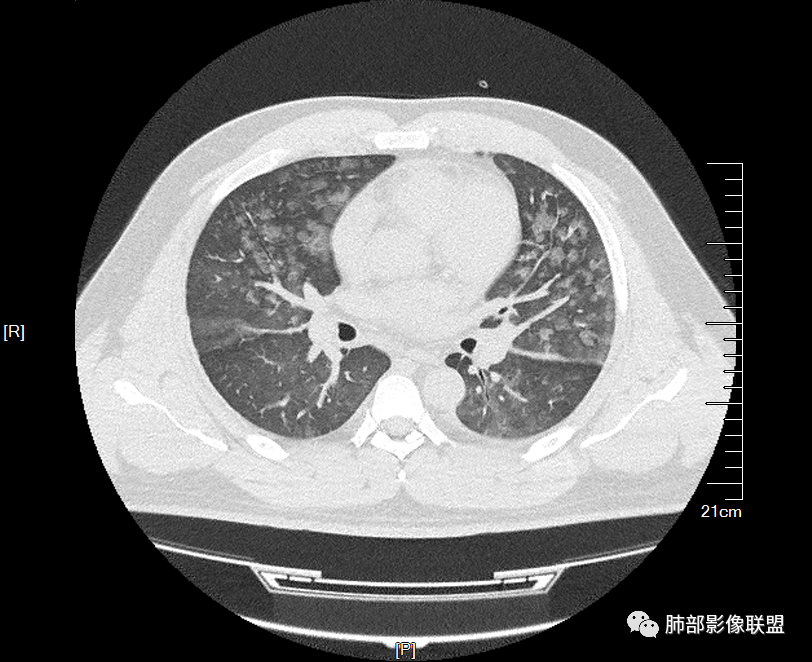

青年男性,无呼吸道症状,CT双肺弥漫性磨玻璃影,无规律分布,边缘清楚,有小叶间隔增厚,叶间胸膜增厚,考虑间质相关性病变?过敏?

两肺弥漫向心分布的腺泡结节,部分融合,两肺小叶间隔增厚,血肌肝高,考虑肺泡性肺水肿

青年男性,痛风、肾功能不全病史,双肺多发结节状、斑片状阴影,支气管血管束增粗,可见支气管袖口征,叶间裂及小叶间隔增厚,考虑肺水肿。

年轻男性,痛风史,高血压史,肌酐高,左足痛6天入院。胸CT:双肺多发弥漫性磨玻璃结节影,大小不一,部分融合,上中下肺都有,中内带多,胸膜下少。部分血管束略增粗,小叶内间隔、小叶间隔增厚,下肺明显,左室大。叶裂胸膜增厚。临床有痛风,左足痛6天,考虑:心衰、间质性肺水肿?弥漫性肺泡出血?鉴别:MPA,肺肾综合征,痛风结节等。

青年男性,有肾功能不全史和痛风史,这个影像分布有个典型的特点,全部是以中央间质周围的渗出性改变,这个改变主要就是两种可能,一种是肾功能不全导致的血管通透性增高导致的肾性肺水肿,一种是出血导致的DAH改变,具体是哪种,影像上不好简单的鉴别,需要结合更多临床资料综合分析。

小叶间隔增厚,无明显重力趋势

少量积液,脂肪肝

这里有一点重力趋势

中轴间质稍增厚

中轴间质增厚,小叶间隔增厚,小叶内间质增厚,部分重力作用,双侧对称,胸水,按理淋巴道回流受阻有

肺水肿类病变有